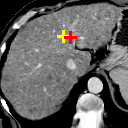

Figure 6: Example comparison among VTN ADDD + inv (c/d), Elastix (e/f), ANTs (g/h) and VoxelMorph-2 (i/j). (a) sections of the fixed image (a CT liver scan); (b) sections of the moving image (another CT liver scan); (c/e/g/i) sections of the warped images and landmark distances; (d/f/h/j) sections of the warped segmentations (white for the fixed and semi-transparent red for the warped) and segmentation IoUs. Crosses indicate the projection of landmarks (L2, L3 and L4 from top to bottom), yellow (lighter) for one in the fixed image, red (darker) for the corresponding one in the moving/warped images. Best viewed in color.

Figure 6 compares different methods listed in Table II, where three landmarks are selected and the sections of the volumes at the height of each landmark in the fixed image are rendered. This means the red crosses (landmarks in the moving and warped images) indicate the projections of the landmarks onto those planes. It should be noted that though the sections of the warped segmentations seem to be less overlapping with those of the fixed one, the Segmentation IoU is computed for the volume and not the sections. It might well be the case that the overlap is not so satisfactory when viewed from those planes yet is better when viewed as a volume. Similarly, overlapping red and yellow crosses do not necessarily imply overlapping fixed and warped landmarks as they might deviate along z𝑧z-axis.